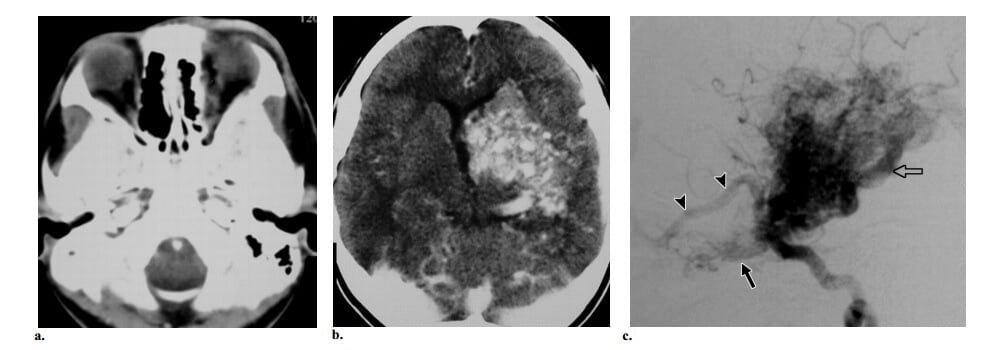

Hình 10: AVF màng cứng Borden type 2 ở phụ nữ 45 tuổi bị mất tri giác đột ngột. (a) Axial CT không cản quang thấy máu tụ thái dương chẩm trái với xuất huyết trong não thất. (b) Axial T2w cho thấy nhiều cấu trúc fliod voids mạch máu dọc theo các rãnh vỏ não của vùng chẩm hai bên. Có phù chất trắng với tăng tín hiệu trên T2W ở thùy chẩm trái. Không thấy nidus. (c) Chụp động mạch hàm trong trái cho thấy AVF màng cứng ở xoang ngang trái được cấp máu bởi động mạch màng não giữa trái. Ghi nhận có huyết khối đi kèm của phần gần và phần xa xoang ngang, tạo thành một “túi riêng biệt” và vì vậy gây ra dòng ngược từ shunt vào các tĩnh mạch vỏ não.

Hình 11: Bệnh moyamoya ở nữ 28 tuổi trải qua hai đợt xuất huyết nội sọ tái phát. (a) Axial CT cho thấy xuất huyết trong não thất. (b) Axial T2W thấy rất nhiều flow voids trong bể quanh gian não và quanh não giữa. Không thấy nidus. (c) Hình chụp động mạch cảnh trong thế trước sau thấy tắc động mạch cảnh trong trên mấu giường yên (mũi tên đặc) với rất nhiều mạch máu bàng hệ nhánh xuyên (đầu mũi tên). Cùng ghi nhận có cấp máu bàng hệ xuyên màng cứng từ động mạch màng não giữa (mũi tên hở). (d). Chụp động mạch cột sống trước sau cho thấy có liên quan các động mạch não sau, cùng với việc không có mạch máu bàng hệ hình khói thuốc lá gợi ý bệnh ở giai đoạn sau.